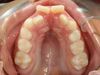

Palais étroit et manque de place pour l'évolution des dents définitives supérieures

Un palais étroit peut entraîner un manque de place pour l'éruption des incisives définitives supérieures, pouvant conduire à une évolution des incisives latérales en arrière des incisives centrales (et donc souvent en inversé d’occlusion avec les dents du bas), voire à une inclusion des canines définitives. Il est par ailleurs le plus souvent lié à une position de langue basse associée à une respiration par la bouche.

Pourquoi traiter ?

Un traitement précoce permet l’évolution normale des dents définitives. Par ailleurs, l’élargissement du palais permet de faciliter le rétablissement d’une respiration nasale et d’une bonne position de la langue, garantes d’une croissance harmonieuse des mâchoires, et participant à la bonne santé générale de l’enfant.